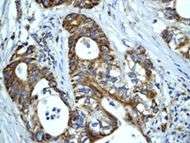

Human Hsp60, the product of the HSPD1 gene, is a Group I mitochondrial chaperonin, phylogenetically related to bacterial GroEL. Recently, the presence of Hsp60 outside the mitochondria and outside the cell, e.g. in circulating blood, has been reported [1], [2]. Although it is assumed that Hsp60 extra-mitochondrial molecule is identical to the mitochondrial one, this has not yet been fully elucidated. Despite the increasing amount of experimental evidences showing Hsp60 outside the cell, it is not yet clear how general this process is and what are the mechanisms responsible for Hsp60 translocation outside the cell. Neither of these questions has been definitively answered, whereas there is some information regarding extracellular Hsp70. This chaperone was also classically regarded as an intracellular protein like Hsp60, but in the last few years considerable evidences showed its pericellular and extracellular residence

HSP60 has been shown to influence apoptosis in tumor cells which seems to be associated with a change in expression levels. There is some inconsistency in that some research shows a positive expression while other research shows a negative expression, and it seems to depend on the type of cancer. There are different hypotheses to explain the effects of positive versus negative expression. Positive expression seems to inhibit “apoptotic and necrotic cell death” while negative expression is thought to play a part “in activation of apoptosis”.[19][20]

As well as influencing apoptosis, HSP60 changes in expression level have been shown to be “useful new biomarkers for diagnostic and prognostic purposes.” [19] According to Lebret et al., a loss of HSP60 expression “indicates a poor prognosis and the risk of developing tumor infiltration” specifically with bladder carcinomas, but that does not necessarily hold true for other types of cancers.[21] For example, ovarian tumors research has shown that over expression is correlated with a better prognosis while a decreased expression is correlated with an aggressive tumor.[21] All this research indicates that it may be possible for HSP60 expression to be used in predicting survival for certain types of cancer and therefore may be able to identify patients who could benefit from certain treatments.[20]